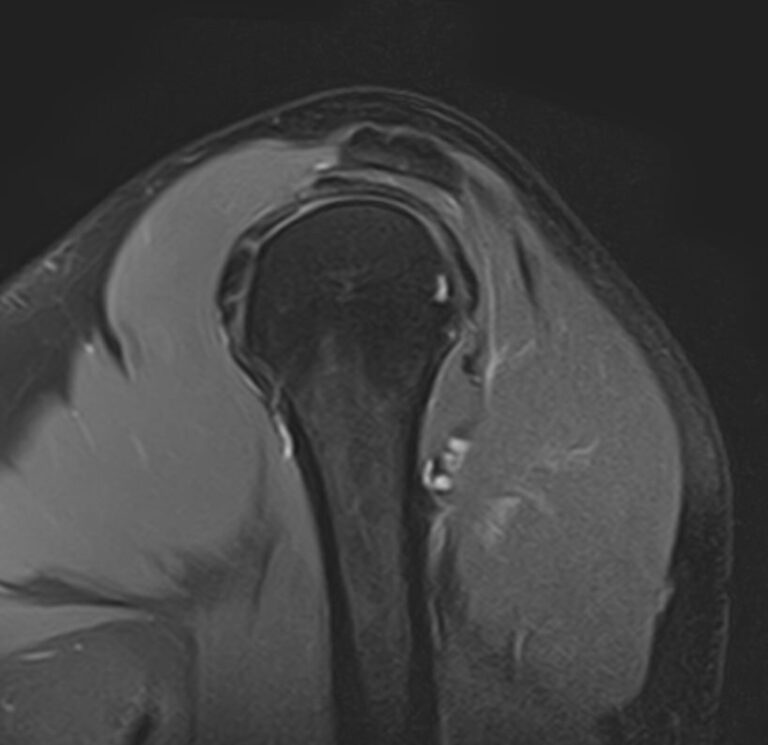

Плечевой сустав является наиболее подвижным сочленением, которое образовано лопаткой и головкой плечевой кости. У сустава нет мощных связок, он укрепляется мышцами плечевого пояса, окружающими его по типу корсета. Суставную капсулу образуют короткие связки, расположенные вокруг сустава. Благодаря такому строению сустав отличается высокой подвижностью, но при этом склонностью к вывихам. Полость сустава заполнена синовиальной жидкостью, питающей хрящи и служащей смазкой для них.

Метод МРТ позволяет оценить состояние всех анатомических областей плечевого сустава,  включая костную структуру, суставную капсулу, полость сустава с выстилающей его синовиальной оболочкой, связки, сухожилия, мышцы и окружающие мягкие ткани.

• Дегенеративно-дистрофические заболевания, в частности деформирующий остеоартроз, при котором происходит истончение хряща на фоне нарушения его питания. В результате развивается дисфункция сустава и деформация костных структур.

• Воспалительные заболевания с поражением как самого сустава (артрит), так и окружающих мягких тканей (синовит, бурсит, тендовагинит).